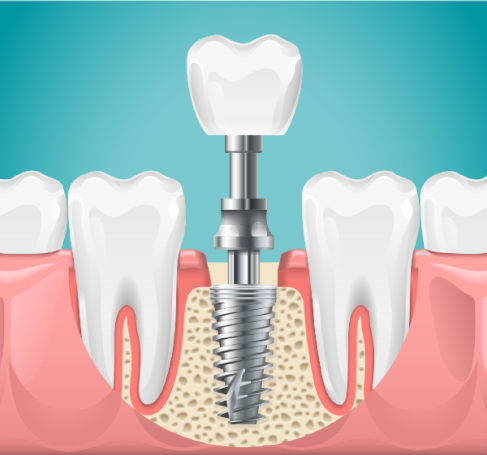

Kronen bieten eine hervorragende Möglichkeit, geschädigte Zähne zu schützen und deren Funktionalität zu verbessern. Sie werden häufig auf eigenen Zähnen angebracht, können aber auch auf Implantaten sitzen.

Zahnersatz auf eigenen Zähnen und Implantaten

Bei den implantatgestützten Versorgungen arbeiten wir vertrauensvoll mit unseren kompetenten Kollegen aus mehreren Greifswalder Oralchirurgie-Praxen zusammen.